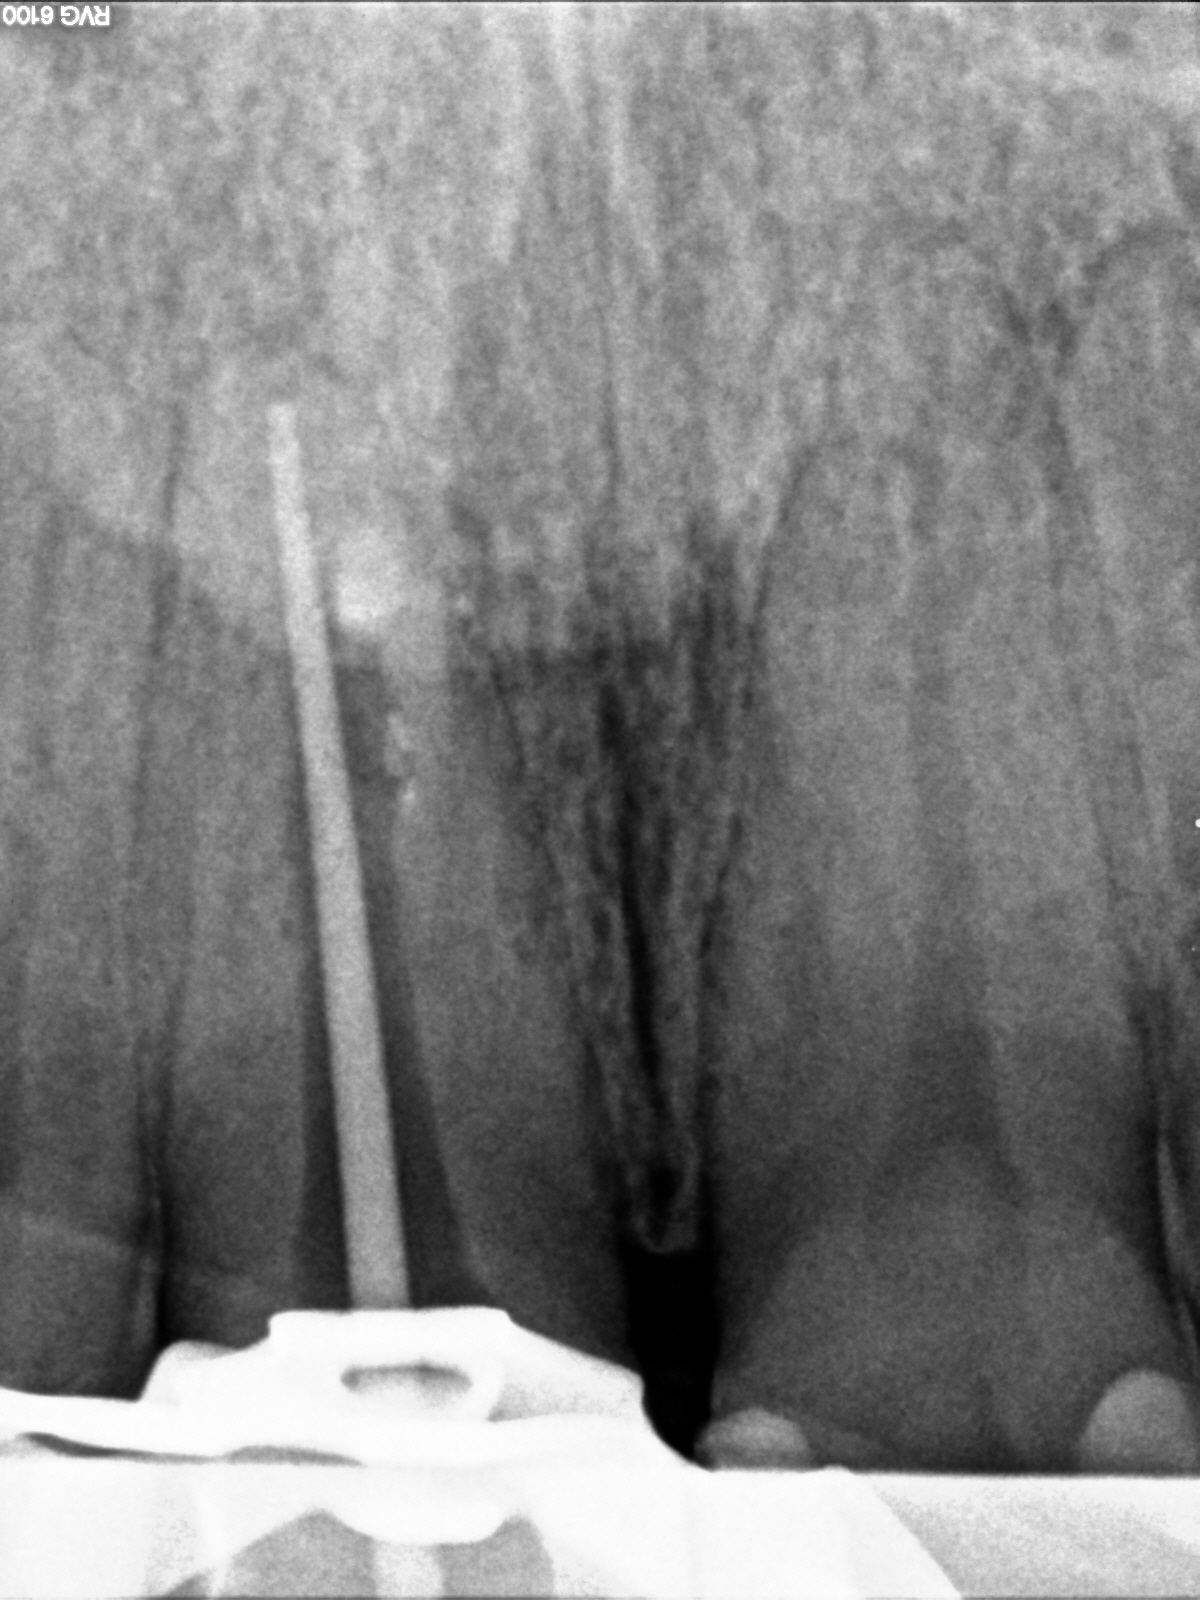

R9

1200 × 1600

Manchmal… (2)

Messaufnahme 2